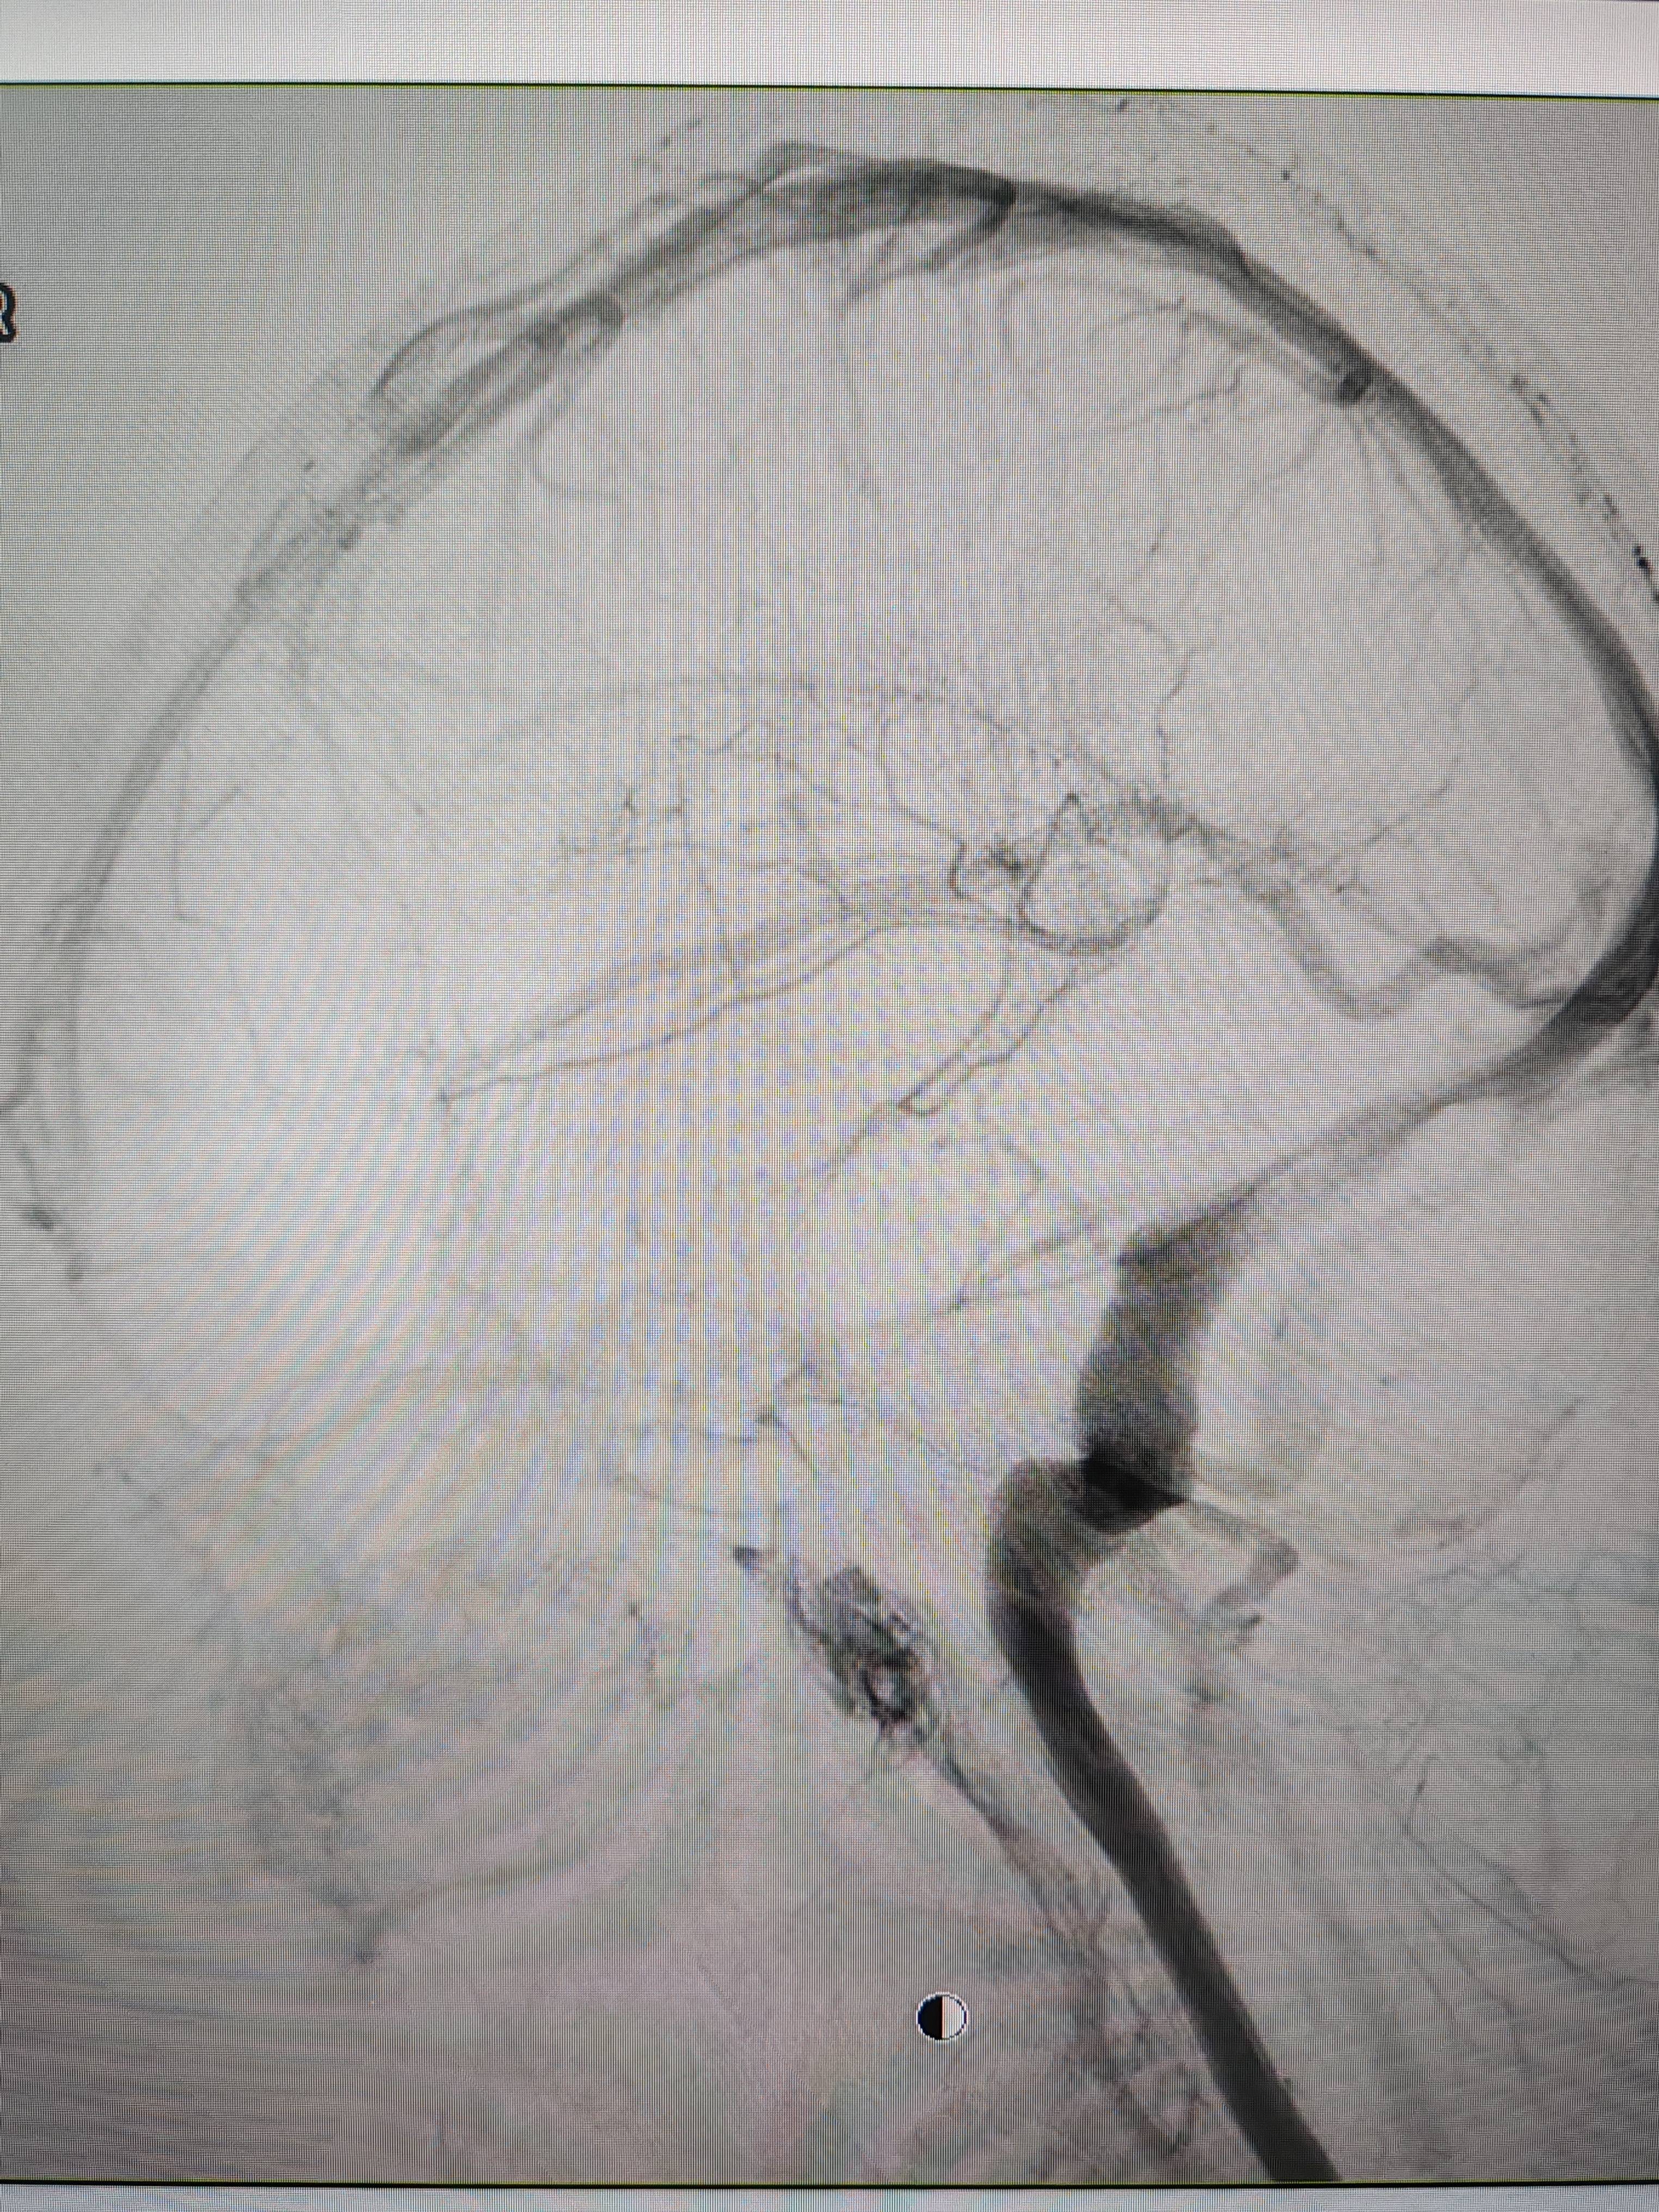

患者造影图像显示,其耳侧静脉窦狭窄皇冠信用網出租足球。 南方+ 欧阳少伟 拍摄

李宝民举例说,通过查体、CT、造影等影像技术的检查,患者赵女士是由于静脉窦狭窄,导致缓慢的静脉血流也出现“湍流”现象,其拐弯、打漩涡、回流产生的声响,又顺着骨传导,传至耳蜗处,进而让患者出现搏动性耳鸣的症状皇冠信用網出租足球。